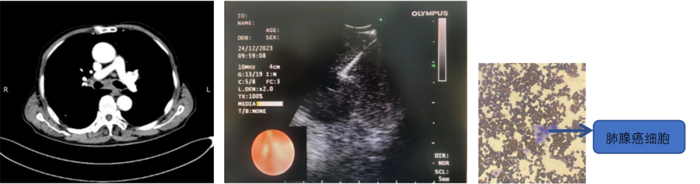

患者,男,70歲,近2個(gè)月來(lái)“活動(dòng)后呼吸困難,近日又出現(xiàn)痰中帶鮮血”,收住院。胸部增強(qiáng)CT見(jiàn)“左肺下葉外周型占位,肺門(mén)、縱膈淋巴結(jié)腫大”。張強(qiáng)主任帶領(lǐng)團(tuán)隊(duì)討論分析患者病情,高度懷疑為腫瘤性病變,且普通電子支氣管鏡獲取組織困難,病變緊貼主動(dòng)脈,經(jīng)皮肺穿刺活檢風(fēng)險(xiǎn)大。為明確診斷及分期,決定為患者實(shí)施支氣管內(nèi)超聲引導(dǎo)下針吸活檢術(shù)(EBUS-TBNA)+電子支氣管鏡下病灶活檢+現(xiàn)場(chǎng)快速評(píng)價(jià)(ROSE)。術(shù)中ROSE快速診斷查找到肺腺癌細(xì)胞,手術(shù)過(guò)程順利。最后病理檢查明確診斷為肺腺癌,為患者的下一步治療確定了方向。

支氣管內(nèi)超聲引導(dǎo)下針吸活檢術(shù),是一種在電子支氣管鏡前端安裝超聲探頭的設(shè)備,結(jié)合專用的吸引活檢針,可在實(shí)時(shí)超聲引導(dǎo)下對(duì)臨近氣管或支氣管的胸內(nèi)病變進(jìn)行活檢。該技術(shù)不僅能實(shí)時(shí)觀察到病灶,同時(shí)可幫助確認(rèn)血管的位置,在提高穿刺診斷陽(yáng)性率的同時(shí)防止誤穿血管,減少風(fēng)險(xiǎn),術(shù)中ROSE進(jìn)一步提高了取材效率,可實(shí)現(xiàn)精準(zhǔn)、高效、安全的明確診斷,又可大大減少對(duì)患者的損傷。(于 雪)